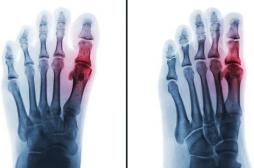

J ai Mal Bras et mains Bras et mains Tête et cou Torse et haut du dos Jambes et pied